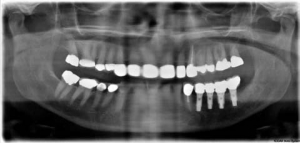

A Key Implant Position For A Fixed Prosthesis: The First Molar Rule

FIGURE 4--A panoramic radiograph from figures 2 and 3.

Treatment planning for implant dentistry in the posterior regions of the mouth is often driven by the existing bone volume in the edentulous sites. As a consequence, distal cantilevers are extended from anterior implants or shorter implants are placed in the posterior regions of the mouth. 1 In the maxillary posterior region, pterygoid and/or zygomatic … Read more